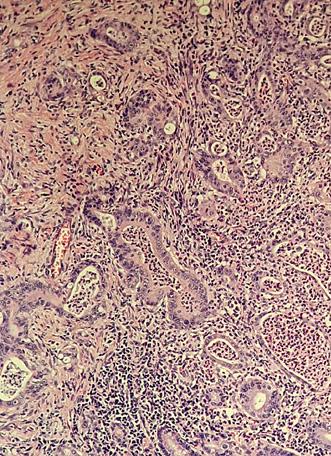

În iulie 2018, pacientul a revenit la control, normoponderal (IMC 20,6 kg/ m2), fiind în remisiune clinică, iar bi ologic în limite normale. S-a efectuat o reevaluare colonoscopică la care s-au identificat pseudopolipi și leziuni cica triceale postinflamatorii la nivelul între gului colon, iar la 25 cm de orificiul anal, un ulcer cu diametrul de 20 mm (Figura 1), din care s-au prelevat multiple biopsii. Aspectul histologic a relevat adenocar cinom colonic moderat diferențiat. La examinarea CT toraco-abdomino-pelvin, s-au vizualizat micronoduli pulmonari nespecifici, o îngroșare parietală la ni velul ceco-ascendentului cu aspect infla mator și o îngroșare parietală asimetrică la nivelul joncțiunii recto-sigmoidiene, sugestivă pentru un substrat tumoral (Fi gura 2).

S-a intervenit chirurgical, efectu ându-se colectomie totală cu ileo-recto anastomoză termino-terminală, cu evo luție postoperatorie favorabilă. Rezultatul histopatologic al piesei de rezecție a fost

de adenocarcinom colonic moderat dife rențiat G2, cu arii de diferențiere muci noasă și invazie perineurală asociată, pT3 pN1a PnI+ LVI+ (Figura 3). În octombrie 2018, s-a inițiat chimioterapia adjuvantă, efectuându-se 8 cicluri CAPOX, în aso ciere cu Filgrastim, încheierea acesteia fi ind marcată de apariția reacțiilor adverse neurologice – parestezii distale la nivelul membrelor. Pacientul a continuat moni torizarea oncologică, la examinările ima gistice ulterioare nefiind decelate semne de recidivă oncologică sau determinări secundare.

Figura 1. Leziune decelată colonoscopic la 25 cm de OA Figura 2: Îngroșare parietală asimetrică la nivelul joncțiunii recto-sigmoidiene Figura 3. Adenocarcinom moderat diferențiat, cu arhitectură tubulară